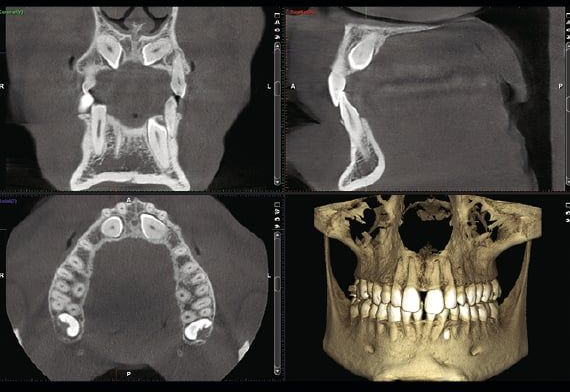

Planmeca

Radiografia panoramica delle arcate dentarie.